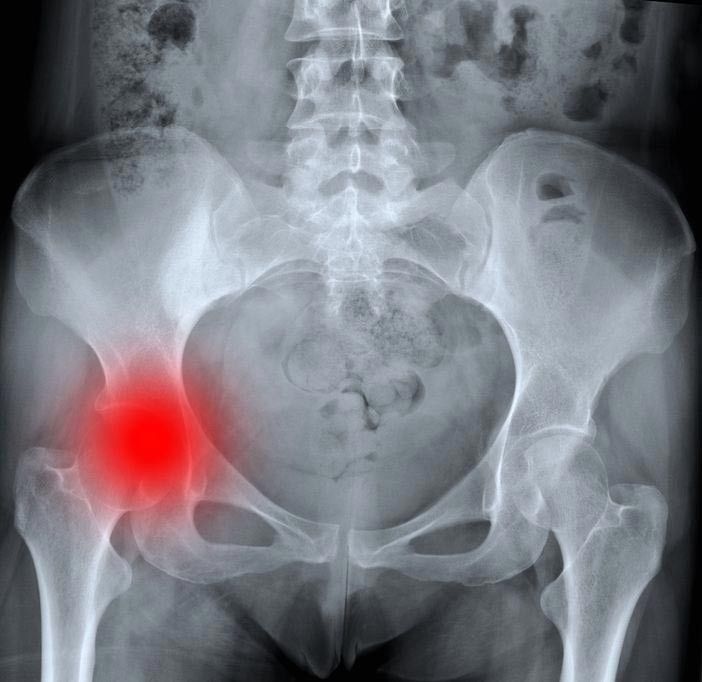

Patah tulang bisa terjadi di bagian mana saja pada tubuh. Panggul menjadi satu bagian tubuh yang sering mengalami patah tulang. Yang di maksud patah tulang panggul adalah patah tulang pada seperempat atas bagian tulang femur (paha). Luas dari patah tulang tersebut bergantung pada gaya/kekuatan dari trauma yang terlibat.

Patah tulang panggul biasanya disebabkan akibat jatuh atau hentakan langsung pada bagian panggul. Beberapa kondisi medis yang dapat menyebabkan patah tulang panggul, seperti:

Ketiga hal tersebut dapat merapuhkan tulang dan membuat panggul lebih berisiko untuk mengalami patah tulang. Pada kasus tertentu, patah tulang panggul masih mungkin terjadi walau seseorang hanya berdiri dan memutar badannya.